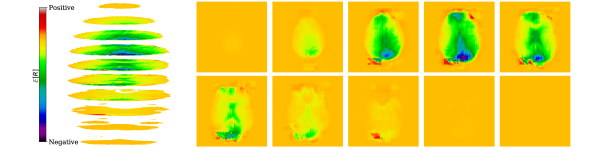

Converging to retrieve near scalp haemodynamical activity. One interesting phenomena that was observed by propagating relevances from the latent representations of the fMRI instance, , to the input, , was that the relevances in sub-cortical areas were neither positive nor negative, yielding residual relevance, as seen in Figure 6. This later observation suggests that haemodynamical activity from these areas does not significantly aids the targeted synthesis. Recall that the regularization term, , is used with the latent EEG and fMRI representations. This is in accordance with the fact that the retrievable information is in its majority next to the scalp, where the electrodes are placed. de Beeck and Nakatani [15] discuss how high frequencies are not able to travel significant distances with obstacles, such as white matter and the scalp, in between. We also report negative relevances on the visual cortex and positive relevances on the occipital and prefrontal lobes. Please note that negative and positive relevances represent relevant features, whereas when one has zero relevance, it means a feature was not relevant for the task. Daly et al. [8] found that neuronal activity retrieved from EEG can reflect the haemodynamical changes in subcortical areas. Here we claim that haemodynamical activity information in areas next to the scalp are relevant to learn the shared latent space.